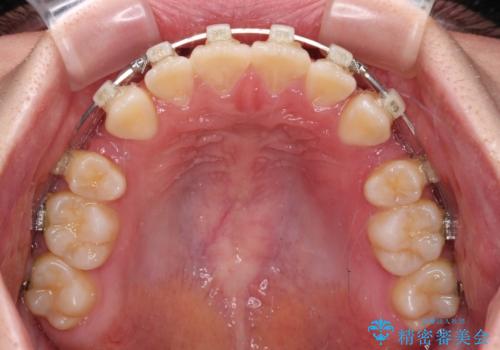

前歯が2本ない ワイヤー装置での抜歯矯正

- 矯正装置

- クリアブラケット

- 下顎前歯欠損による隙間と、上顎前歯の突出感を気にして来院された患者様です。

横顔に出っ歯の印象はありませんでしたが、下顎のスペースと上下前歯の前後位置の大きなズレを改善するために、上顎左右の第一小臼歯2本を抜歯しすることとしました。

口元が引っ込みすぎないようにするために、上下ともに臼歯を前方に移動させる必要があり、インビザラインでは対応できないため、表側のワイヤー装置にて矯正治療を行うこととしました。